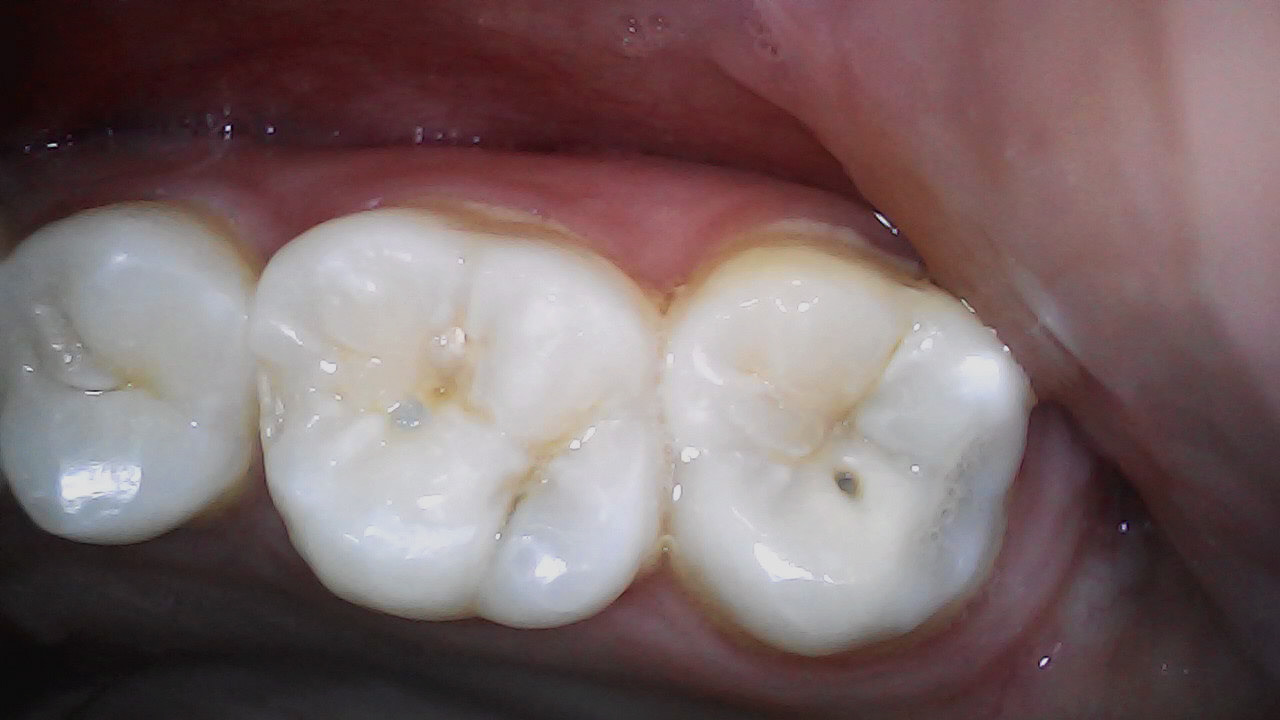

Final